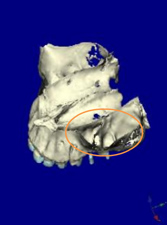

CTデータより3D画像を構築

左上に2本のインプラントを計画

上顎咬合面観